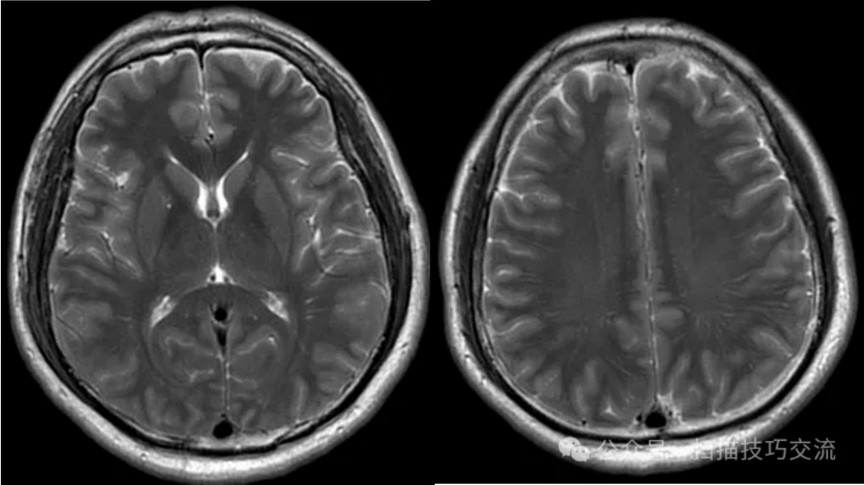

•汗腺分泌:正常,皮肤划痕正常反应。 •尿便障碍:无。性功能障碍无。 •专科情况:正常。不逐一罗列。 •辅助检查:01-05颅脑CT提示:1,上矢状窦、双侧横窦密度较高,请结合临床,必要时进一步检查;2,双侧脑室后角可疑稍高密度影,右顶叶局部脑沟密度可疑增高,建议进一步检查。 •初步诊断:静脉窦血栓

临床申请:颅脑平扫,静脉成像,磁敏感成像,颅内静脉血管黑血成像。

图像不逐一罗列,未见异常。